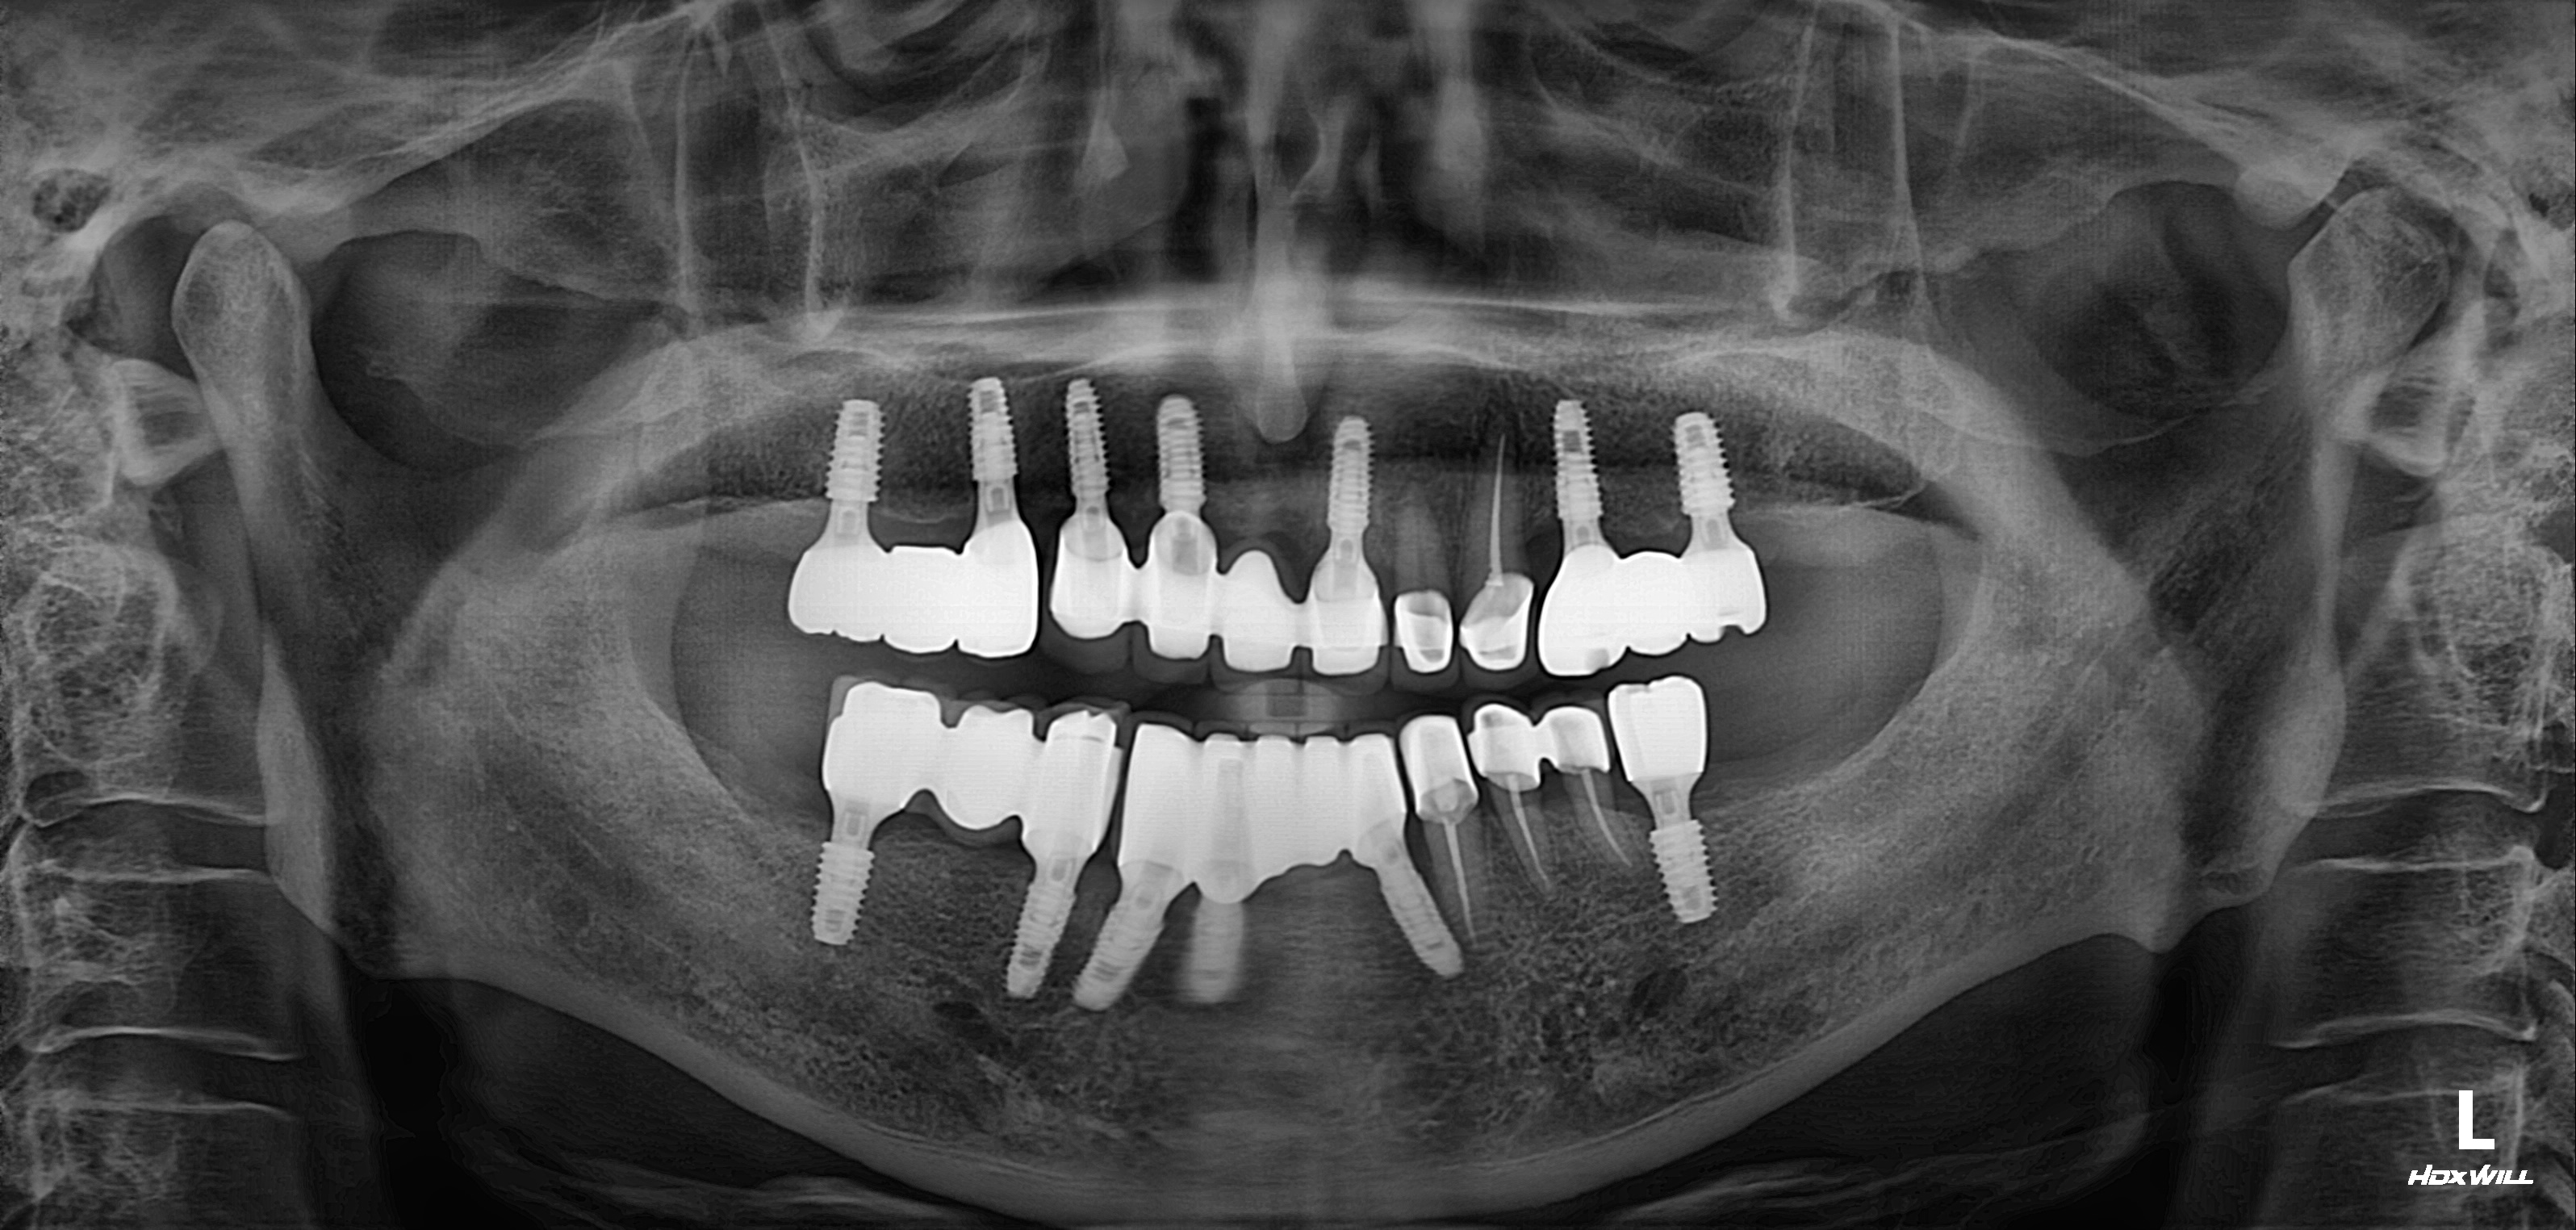

전악 임플란트 식립사례

임플란트